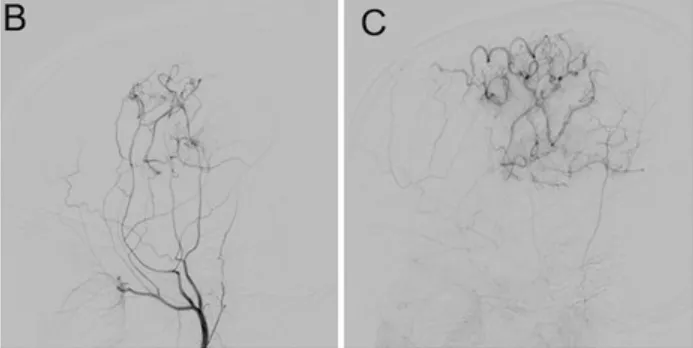

第一次手术术后6个月复查,新血管通畅,小智的偏瘫症状完全消失,又能正常上学、玩耍了。

在6个月的随访中,DSA显示旁路通畅,左大脑中动脉区域的血流完全改善。(图B和C)